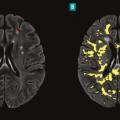

La sclérose en plaques (SEP) est une maladie neuro-inflammatoire chronique du système nerveux central (SNC). Elle est caractérisée par la présence de lésions (ou plaques) au niveau du cerveau et/ou de la moelle épinière et/ou des nerfs optiques. Au sein de ces lésions inflammatoires, la gaine de myéline entourant les axones des…

La sclérose en plaques (SEP) est une maladie inflammatoire et dégénérative du système nerveux central qui concerne environ 120 000 personnes en France. Elle débute habituellement chez l’adulte jeune, en moyenne vers 30 ans, mais peut apparaître à des âges plus extrêmes, rendant l’évocation du diagnostic plus difficile et,…

En dépit de mécanismes auto-immuns incontestés impliqués dans la physiopathologie de la maladie, la sclérose en plaques est de plus en plus considérée comme une pathologie neurodégénérative. Sur le plan clinique, la composante auto-immune se traduit par la survenue de poussées. Sur le plan paraclinique, il s’agit de l’apparition de…